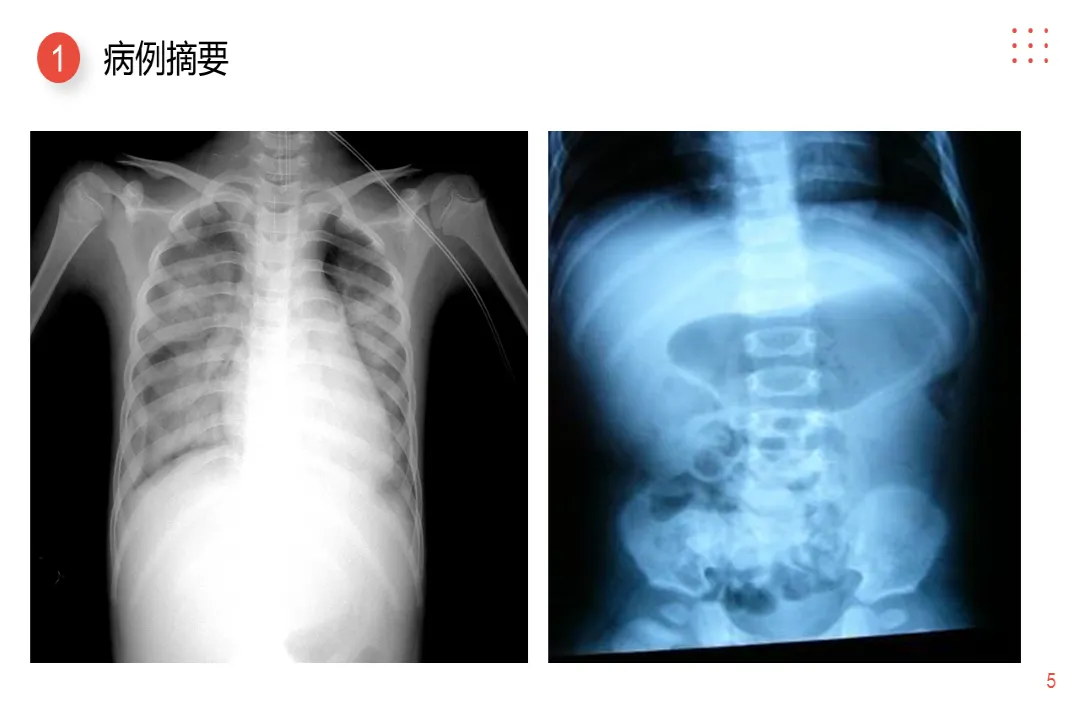

>【医护PPT】小儿肠套叠护理查房

【医护PPT】小儿肠套叠护理查房

01 病例摘要